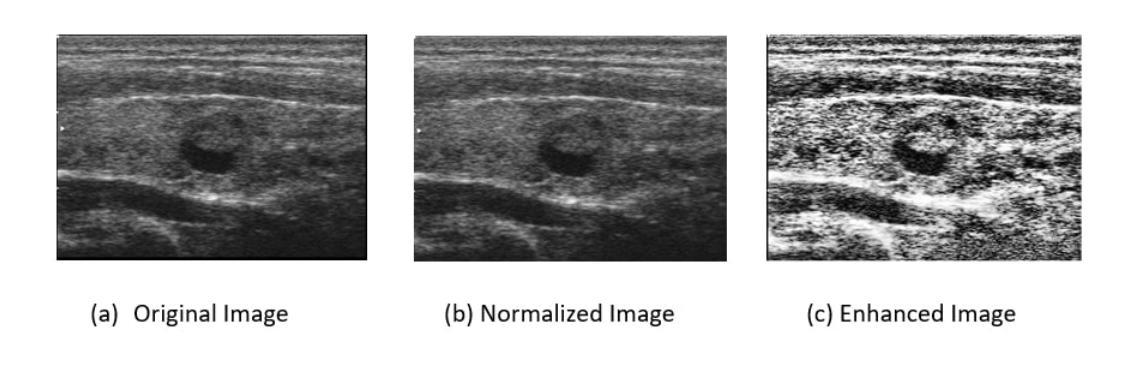

In this study, we develop a new CAD system for accurate thyroid cancer classification with emphasis on feature extraction. Prior studies have shown that thyroid texture is important for segregating the thyroid ultrasound images into different classes. Based upon our experience with breast cancer classification, we first conjuncture that the Discrete Cosine Transform (DCT) is the best descriptor for capturing textural features. Thyroid ultrasound images are particularly challenging as the gland is surrounded by multiple complex anatomical structures leading to variations in tissue density. Hence, we second conjuncture the importance of localization and propose that the Local DCT (LDCT) descriptor captures the textural features best in this context. Another disadvantage of complex anatomy around the thyroid gland is scattering of ultrasound waves resulting in noisy and unclear textures. Hence, we third conjuncture that one image descriptor is not enough to fully capture the textural features and propose the integration of another popular texture capturing descriptor (Improved Local Binary Pattern, ILBP) with LDCT. ILBP is known to be noise resilient as well. We term our novel descriptor as Binary Pattern Driven Local Discrete Cosine Transform (BPD-LDCT). Final classification is carried out using a non-linear SVM. The proposed CAD system is evaluated on the only two publicly available thyroid cancer datasets, namely TDID and AUITD. The evaluation is conducted in two stages. In Stage I, thyroid nodules are categorized as benign or malignant. In Stage II, the malignant cases are further sub-classified into TI-RADS (4) and TI-RADS (5). For Stage I classification, our proposed model demonstrates exceptional performance of nearly 100% on TDID and 97% on AUITD. In Stage II classification, the proposed model again attains excellent classification of close to 100% on TDID and 99% on AUITD.